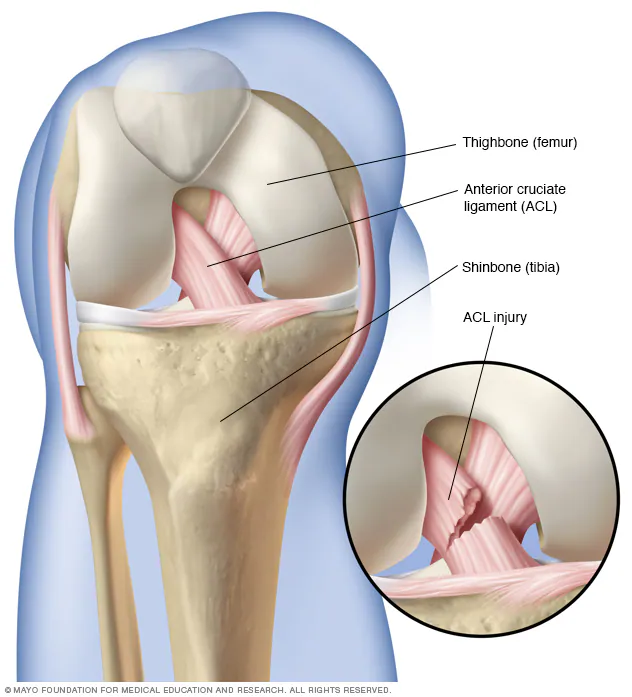

An ACL (anterior cruciate ligament) injury is a common and potentially serious knee injury, especially among athletes and physically active individuals. It…